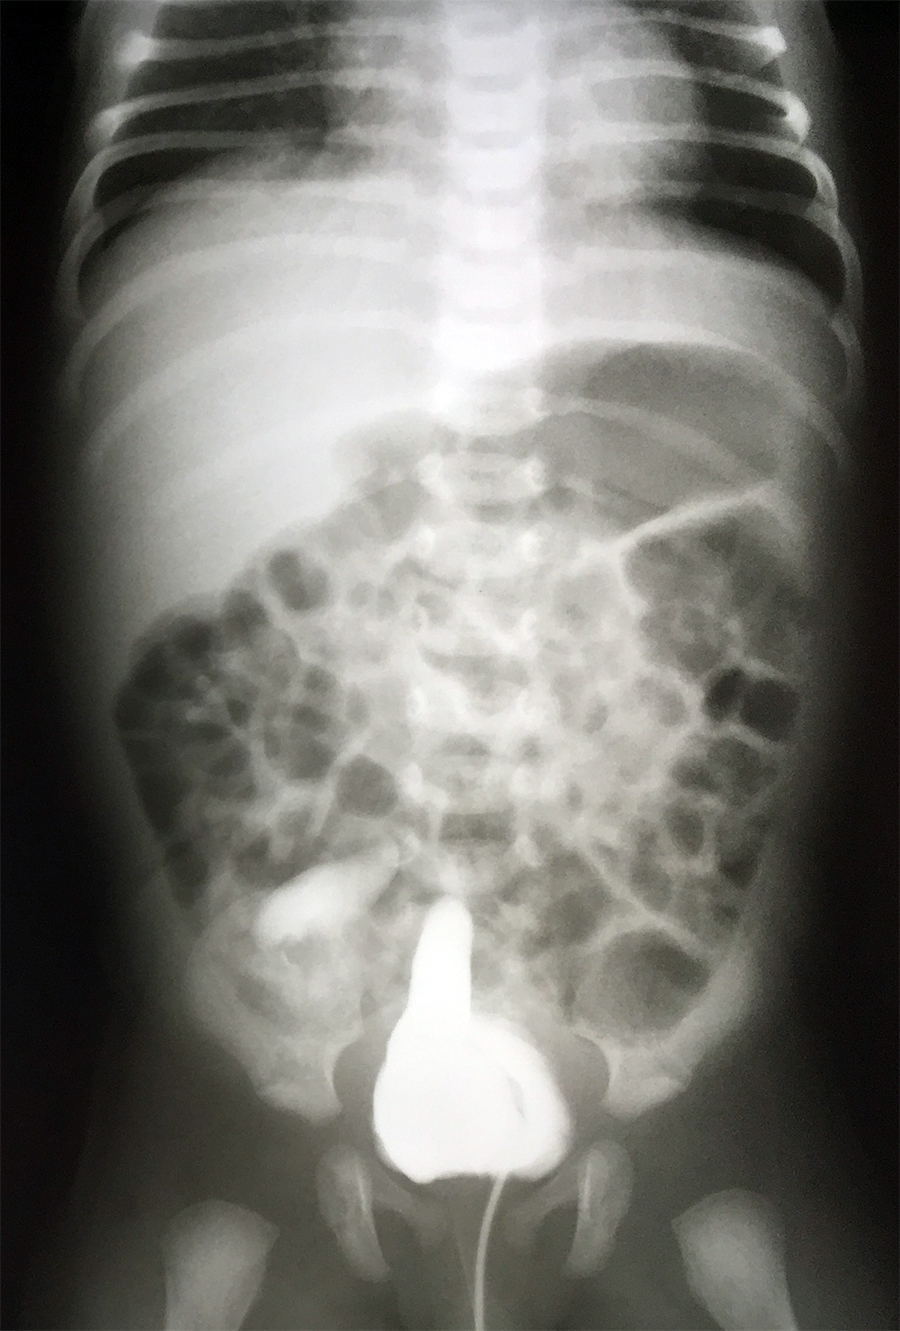

Otrzymujesz do opisania poniższe zdjęcia.

Pacjentką jest 3-letnia dziewczynka. Nie możesz doczytać rozpoznania na skierowaniu.

- Jakie badanie przedstawiają obrazy?

- Czy widzisz jakieś nieprawidłowości? Jak je nazwiesz?

- Na jakim oddziale najprawdopodobniej przebywa pacjentka? Na Wasze odpowiedzi czekam w komentarzach pod zdjęciami!

Badanie: cystouretrografia mikcyjna. Odpływy pęcherzowo-moczowodowe obustronnie. Po stronie lewej odpływ do moczowodu, miedniczki nerkowej i kielichów z poszerzeniem moczowodu (III stopień wg. klasyfikacji odpływów pęcherzowo-moczowodowych). Po stronie prawej odpływ do moczowodu, miedniczki nerkowej i kielichów, moczowód znacznie poszerzony o krętym przebiegu, zarysy kielichów wygładzone (stopień V). Dziewczyna najprawdopodobniej przebywa na oddziale nefrologii dziecięcej.

Moim zamysłem było zwrócenie Państwa uwagi na wspomniane właśnie odpływy pęcherzowo-moczowodowe. Potraficie Państwo wymienić choćby 2 metody leczenia zabiegowego odpływów?